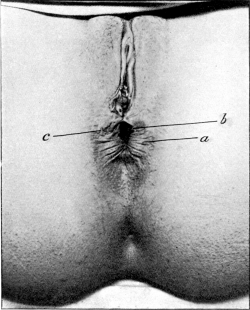

| 30. | Complete Laceration of the Perineum | 127 |

| 31. | Long-handled Sharp-pointed Scissors curved on the flat | 128 |

| 32. | Complete Laceration of the Perineum | 128 |

| 33. | Complete Laceration of the Perineum | 129 |